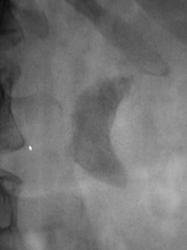

Пол пациента: Мужской пол Тип патологии: Другое Область исследования: Мочеполовая система Методы исследования: Rg Пациент направлен в рентгеновский кабинет для производства внутривенной урографии с подозрением на опухоль левой почки. Произведено стандартное исследование. Ваше мнение коллеги? Вс, 24/05/2009 - 21:05 #1 Андрей Юрьевич Не на сайте Был на сайте: 1 неделя 4 дня назад Зарегистрирован: 16.11.2008 - 22:16 Публикации: 18098 Такой можно и коралловидным назвать. Андрей Юрьевич Пнд, 25/05/2009 - 10:47 #2 v1tal Не на сайте Был на сайте: 4 года 9 месяцев назад Зарегистрирован: 07.06.2008 - 19:41 Публикации: 1779 А сколько лет пациенту? В анамнезе туберкулеза нет? "Знаешь, у некоторых врачей есть комплекс мессии — им необходимо спасать мир. А у тебя комплекс Рубика — тебе необходимо решать головоломки." Пнд, 25/05/2009 - 15:45 #3 Катенёв Валенти... Не на сайте Был на сайте: 7 лет 3 недели назад Зарегистрирован: 22.03.2008 - 22:15 Публикации: 54876 В анамнезе туберкулёза (легочного) нет. Пациенту 42 года. Мочу, сейчас, у всех пациентов с "урологической патологией" на МБТ и "смотрят и сеют". А какое мнение коллег по поводу правой почки?

Такой можно и коралловидным назвать.

А какое мнение коллег по поводу правой почки?